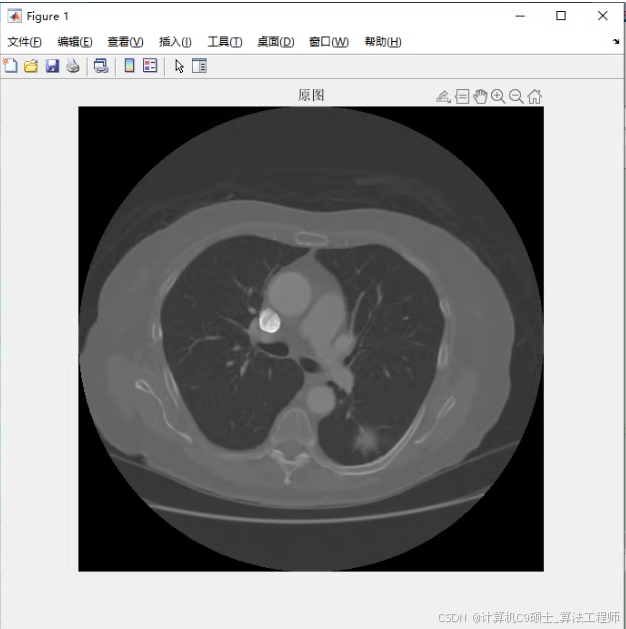

1、读取图像。读取原始dicom格式的CT图像,并显示,绘制灰度直方图;

读取图像

读取图像:read_dicom.m负责读取DICOM图像并显示,同时绘制灰度直方图。